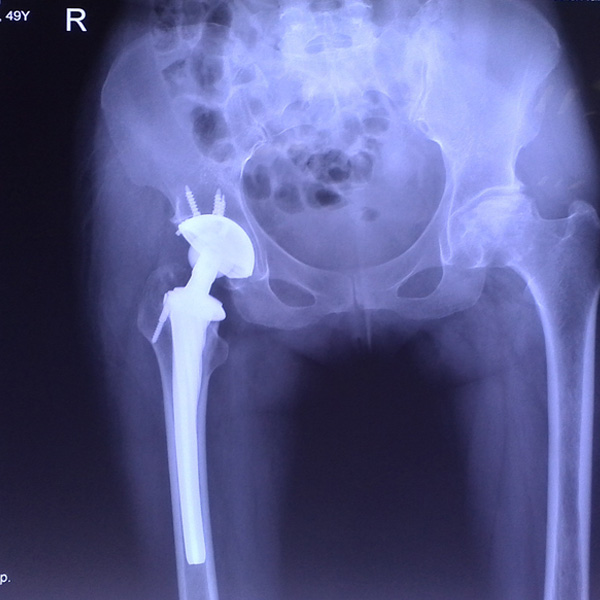

髖關(guān)節(jié)翻修

患者蘇某,女性,11年前因“左髖關(guān)節(jié)屈曲攣縮畸形”行左側(cè)人工全髖關(guān)節(jié)置換,近來(lái)感覺(jué)左髖關(guān)節(jié)疼痛,不敢行走,經(jīng)“攜生醫(yī)療平臺(tái)”就診于哈......